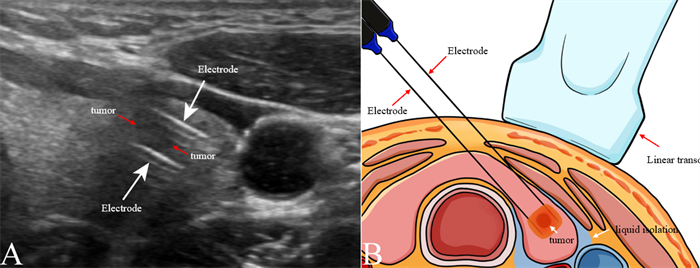

纳秒刀消融PTMC示意图。

纳秒刀治疗全程在超声引导下进行,仅需通过直径2mm的细小电极针穿刺进入甲状腺,无需开刀,颈部不会留下任何疤痕。对于注重外观的年轻患者而言,这种微创方式既可以减少手术创伤,又避免了疤痕带来的心理负担。研究中,患者术后恢复快,短期内即可回归正常工作和生活,大幅提升了生活质量。

此次研究中,纳秒刀消融全程依赖超声引导,这一技术保障了治疗的精准性和安全性。超声作为实时、无创的影像手段,能够清晰显示肿瘤的位置、大小、形态,以及与喉返神经、气管等周围结构的关系,帮助医生精准定位电极位置,确保消融范围完全覆盖肿瘤,同时避开重要组织。术后即刻通过超声造影(CEUS),可直观判断消融效果,若消融范围不足可及时补充治疗,进一步提升疗效。